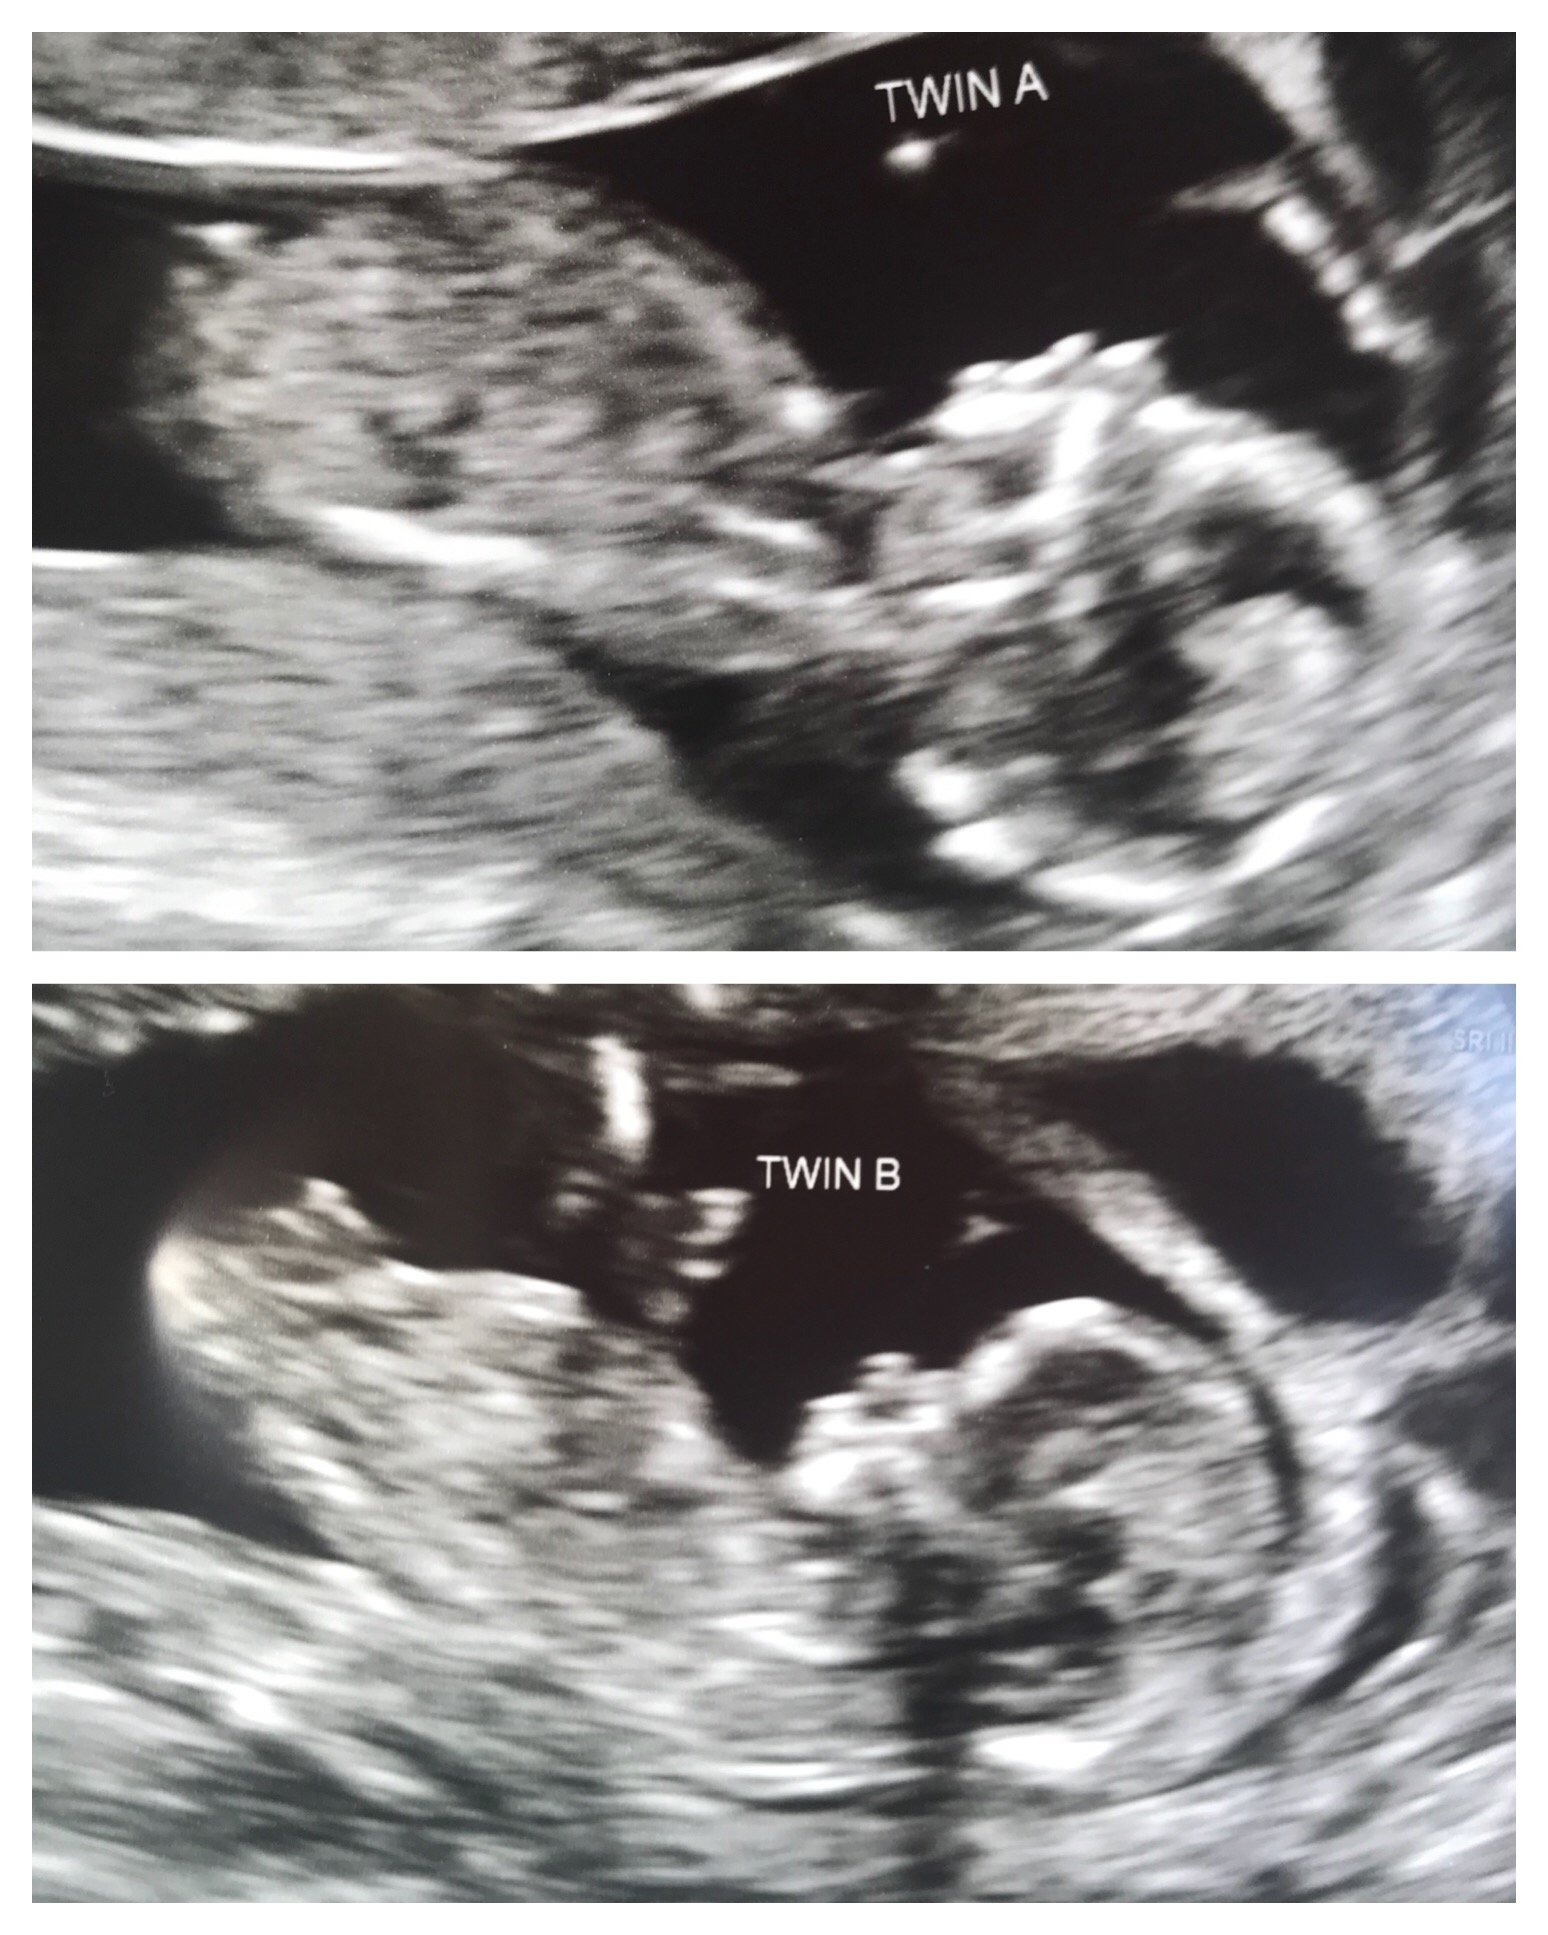

excited to finally get a pic up here! from this morning, confirmed identical twins, 12w exactly and measuring right on track. both were camera shy, but also cooperative for the ultrasound tech (rolled over at the right time). apologies to those who hate 3d pics, but this was the only pic i got of both at the same time.